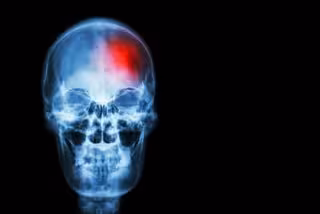

La presión arterial baja, asociada a mayor riesgo de muerte tras ictus

Archivo - Ictus